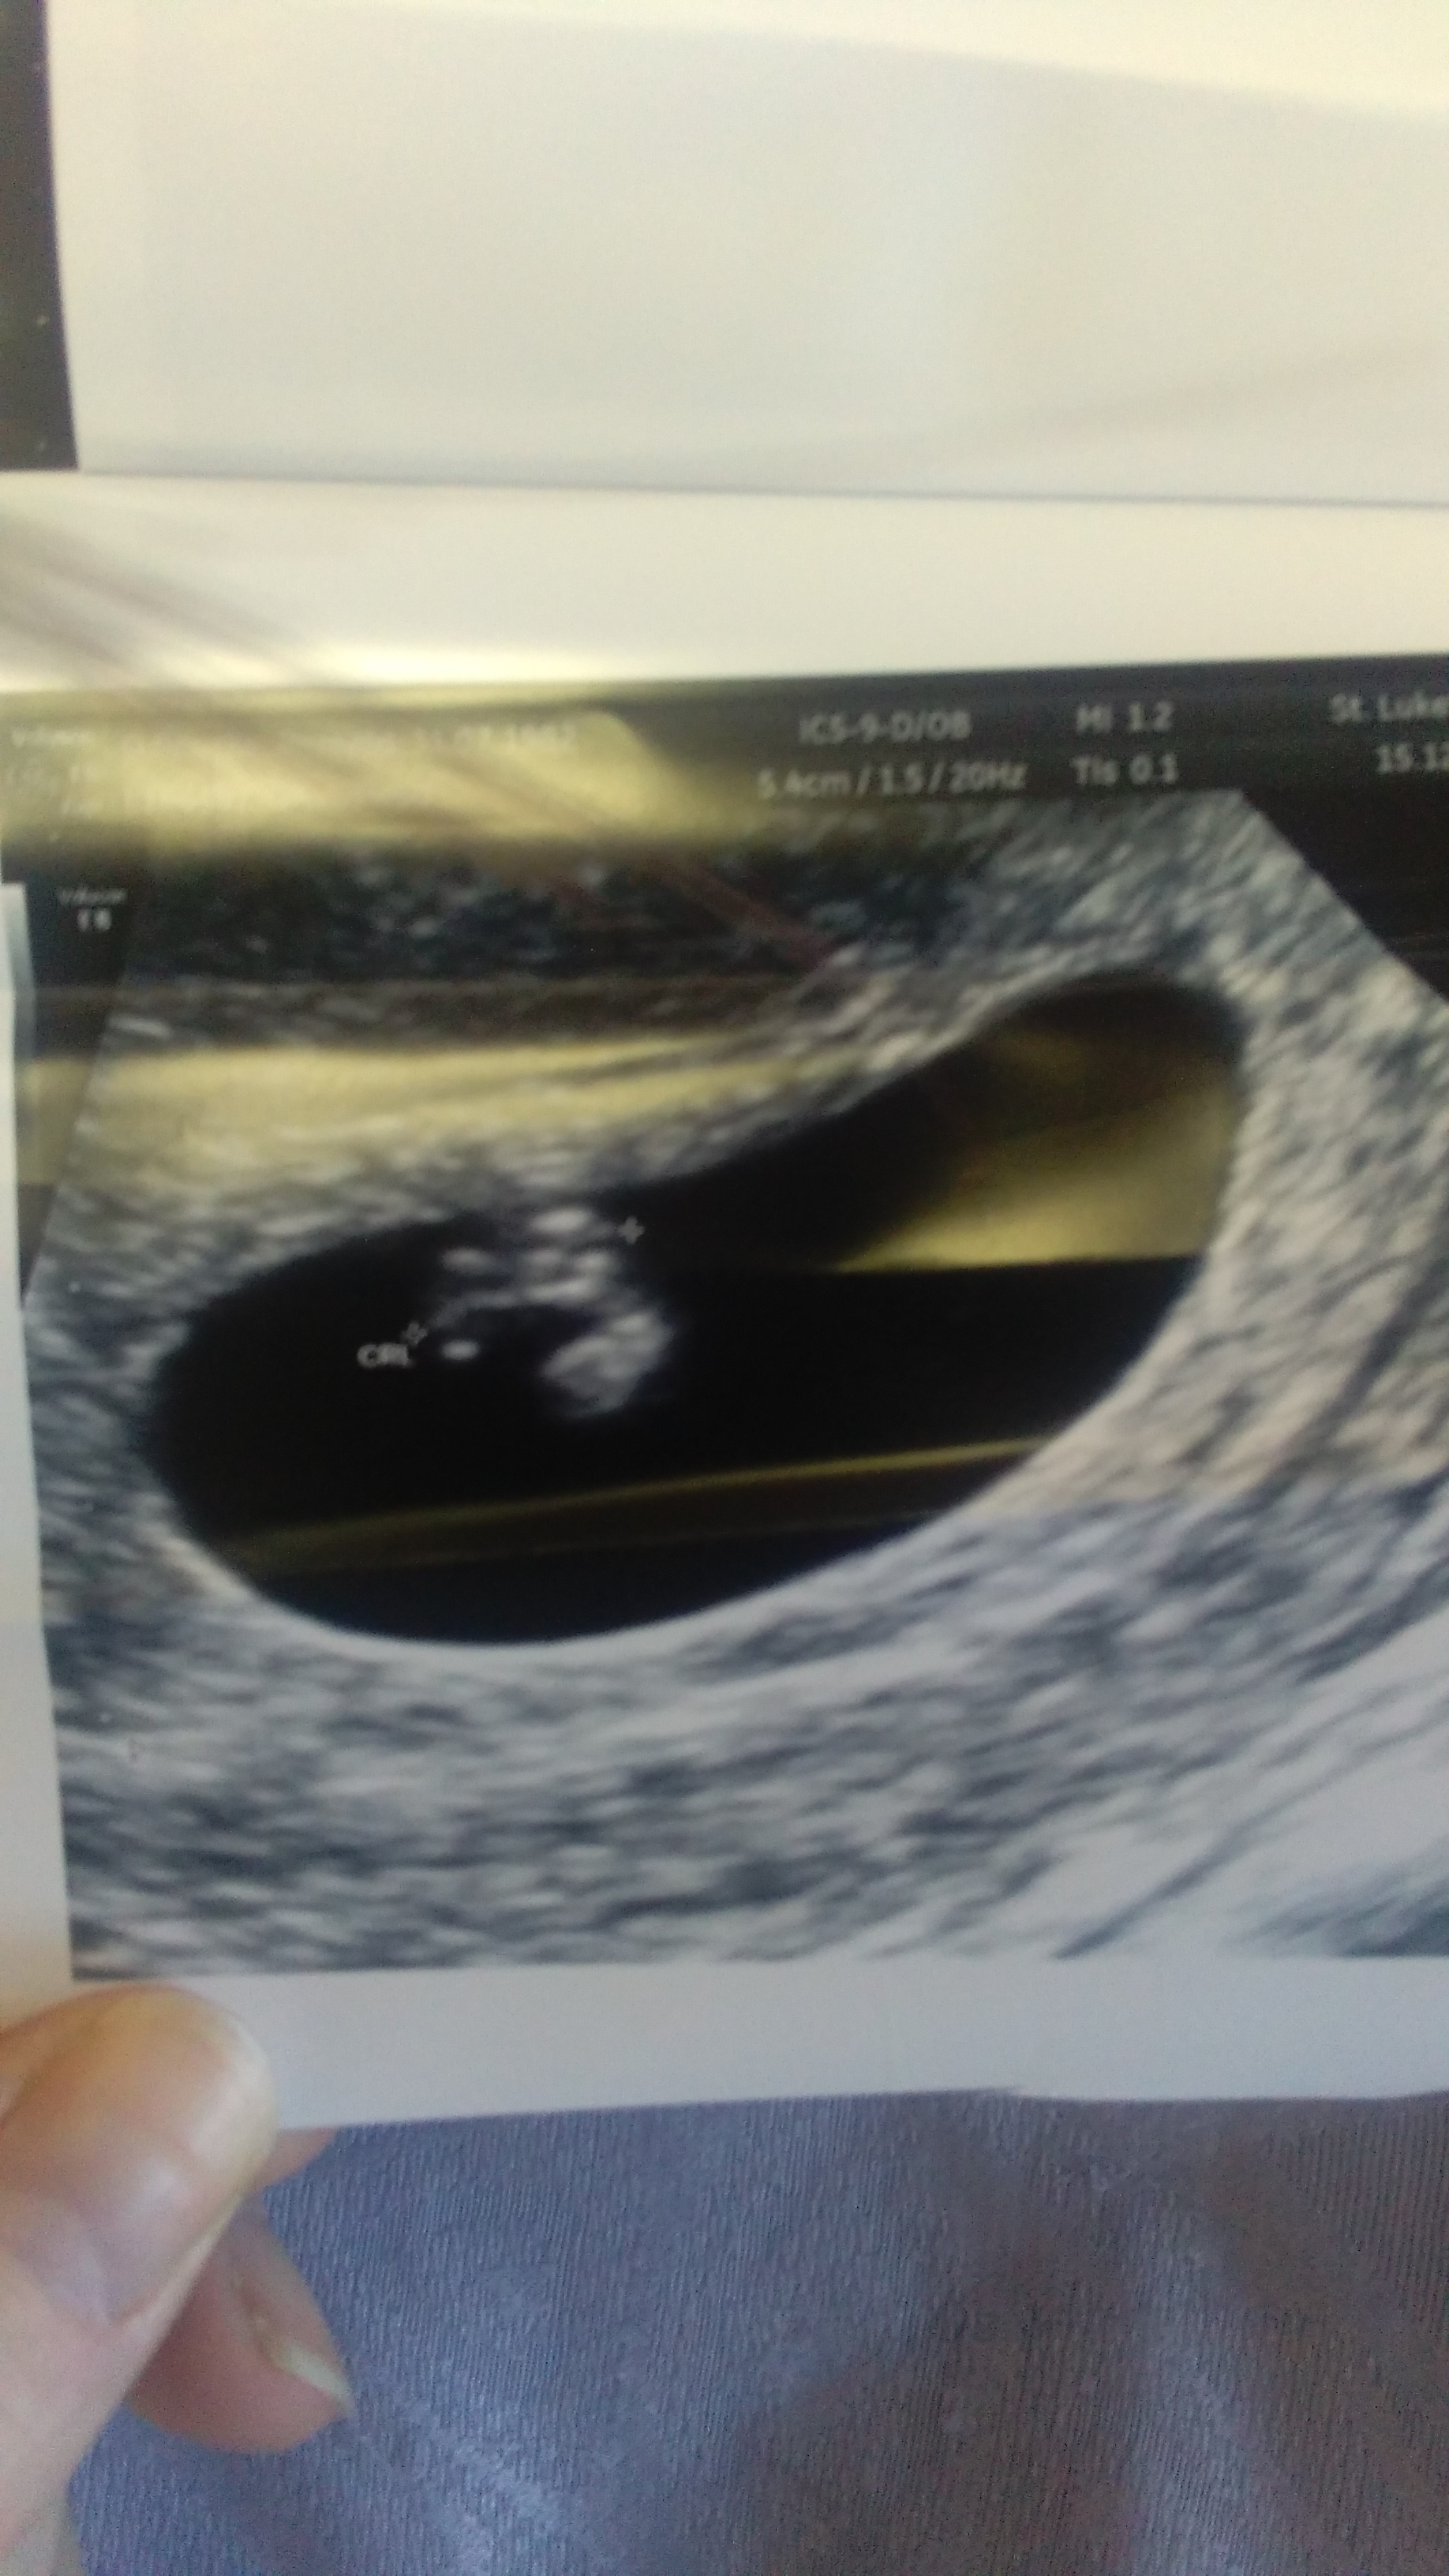

I'm 12 weeks today and had scan this AM. First PIC is of DS1 at 14 weeks second picture is of this bubs today at 12 weeks. Will be asking for a nub shot next week at 13 week scan but won't be having anatomy scan til mid March which feels ages away so for some fun please have a guess xxAttachment 29454Attachment 29455